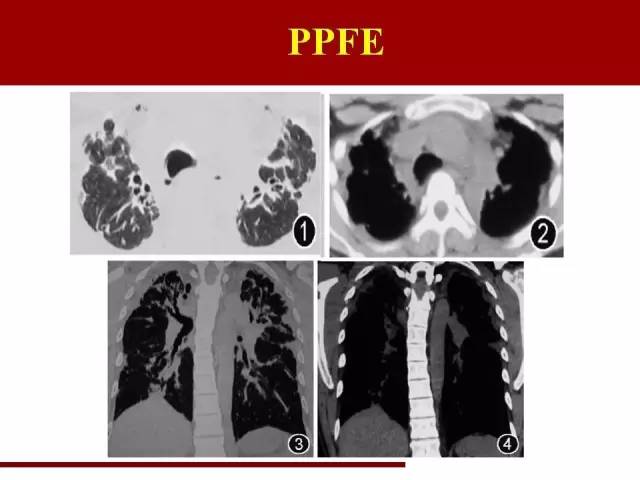

最后一类是一个年轻的间质性肺炎,2004年命名的,所以在2002年那一版分类里面没有这一类

PPFE近些年也逐渐被重视,报道逐渐增多

PPFE在间质性肺炎里面两个唯一:唯一主要同时累及肺和胸膜的间质性肺炎,唯一倾向中上肺野分布的间质性肺炎

袁怀平:

中上肺野肺纤维化伴胸膜增厚,容积缩小

需要与尘肺,特别是石棉肺鉴别

主要鉴别点在于石棉肺的胸膜斑更明显,并且伴有钙化